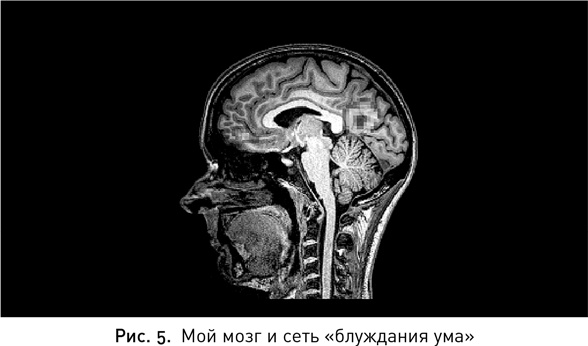

Итак, я свою «зону» нашла. Что это за состояние? Нейробиологи уже много лет пытаются ответить на этот вопрос. Майк уверен, что это такое состояние внимания, в котором соблюден идеальный баланс между активностью дорсальной сети внимания и другим участком мозга, так называемой сетью пассивного режима работы мозга. Эта сеть активируется, когда наш ум блуждает, мы мыслим творчески или просто не думаем ни о чем конкретном.

Иллюстрация к книге — Мой продуктивный мозг. Как я проверила на себе лучшие методики саморазвития и что из этого вышло [i_006.jpg]

Недавние эксперименты бостонской команды исследователей показали, что люди намного чаще допускали ошибки в тесте с Бетти, когда наиболее активной была сеть блуждания ума; результаты улучшались, когда в работу включалась сеть внимания. Хотя избыточная активность любой из них приводила к обратному эффекту — испытуемые не могли надолго сосредоточиться на выполнении задания‹‹2››.

Так что идеальное состояние, к которому стоит стремиться, — это не полное выключение сети блуждания ума. Эта сеть развилась не без причины — скорее всего, для решения связанных с охотой и собирательством задач. Состояние блуждания ума позволяет сканировать окружение, пока не появится что-то интересное, — очень полезный навык в условиях непредсказуемости. Сегодня мы используем эту же сеть, когда ищем новые идеи или когда голове нужно передохнуть. Кроме того, длительное поддержание полной концентрации истощает организм. Получается, чтобы сохранять внимание на долгие часы, лучше всего давать мыслям иногда отклоняться от курса — просто надо вовремя возвращать их в нужное русло.